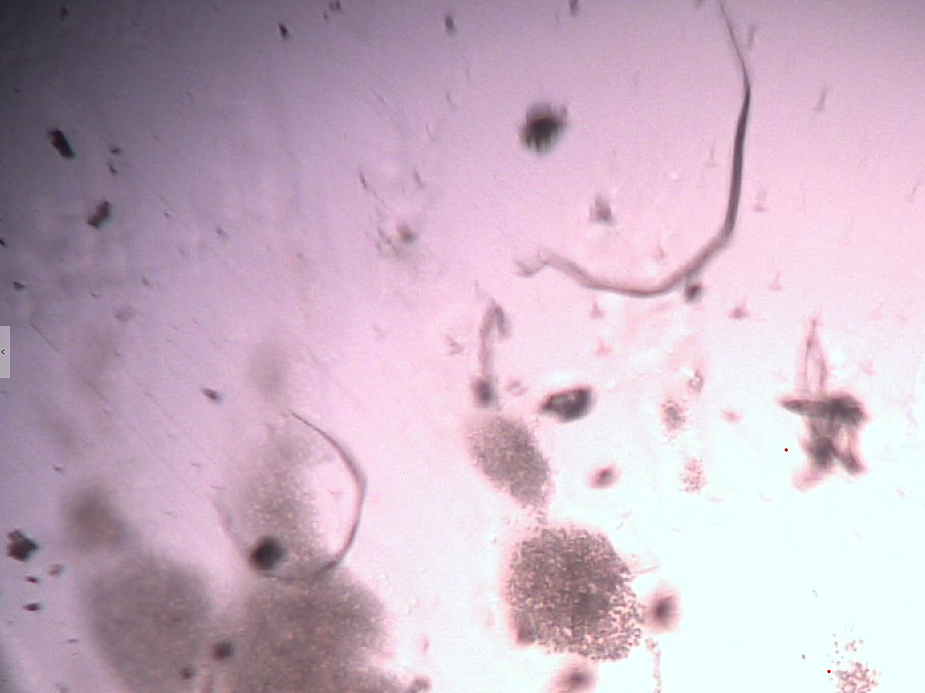

2. The micrograph below shows a symplast or a micro clot of enlarged red blood cells or a blood clot observed using a compound pHase contrast light microscope at 1500x magnification. These micro clots are now commonly seen in the live unstained blood of humans and animals due to acidic/toxic poison now found in food, water, air, vaccines, nutritional supplements and legend drugs. The hemoglobin, the molecule of the red blood cells adsorbs and absorbs metabolic, dietary, respiratory and environmental acidic poisonous waste in order to protect the delicate pH balance of the vascular fluids at 7.365 pH and -20.5 mV and the interstitial fluids that surround all body cells at a 8.4 pH and -80 mV. The red blood cells NOT the white blood cells are the primary protectors of the body cells that make up all organs, glands and tissues. White blood cell are secondary to red blood cells in providing immunity which is a major oversight in current medical microbiology.

3. A large symplast of magnetic nano graphene oxide observed in the live unchanged and unstained capillary blood using pHase Contrast Microscopy of a VAXXinated male.

4. Ferric oxide with lactic and sulphuric acid crystals observed in the live capillary blood from a VAXXinated male using Brightfield, pHase contrast microscopy and confirmed with UV absorbance and Fluorescence Spectroscopy, Scanning Electron Microscopy, Transmission Electron Microscopy, Energy Dispersive Spectroscopy, X-ray Diffractometer and Nuclear Magnetic Resonance instruments.

5. A large symplast of Nano Graphene oxide particulates observed in the live unchanged and unstained capillary blood of a VAXXinated female with metastatic lung and brain cancer patient after chemotherapy.

6. A large symplast of Nano Graphene Oxide observed in the live unchanged capillary blood under pHase contrast microscopy of a UNVAXXinated female. I call these symplasts of graphene, ” Graphene Atomic Bombs”

7. Graphene oxide in the center of what appears as a vulgaris bulgarus parasite at 1500x magnification observed in the live capillary blood under phase contrast microscopy in a VAXXinated female.